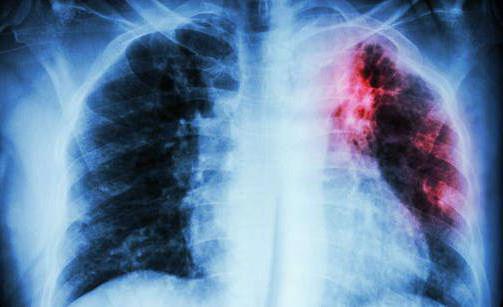

В большинстве случаев палочки Коха поражают легкие, но также существуют и другие виды недуга: туберкулез кишечника, гортани, мочеполовой системы, костей и кожи. Болезнь трудно поддается диагностике на начальных стадиях развития, что усложняет дальнейшее лечение. Прививка от туберкулеза способствует выработке антител и не дает развиться патогенным клеткам, попавшим в организм.

Положительная реакция: необходимые меры

Положительная реакция на Д-тест у взрослого человека предполагает серьезное обследование. Пациенту показана рентгенологическая и лабораторная диагностика (в том числе проба Манту). Ребенку назначают рентгенографию легких (облучение при ней меньше, чем при флюорографии, а патологии легких просматриваются лучше). Это оправдано: по медицинским показаниям рентген показан даже женщинам в интересном положении.